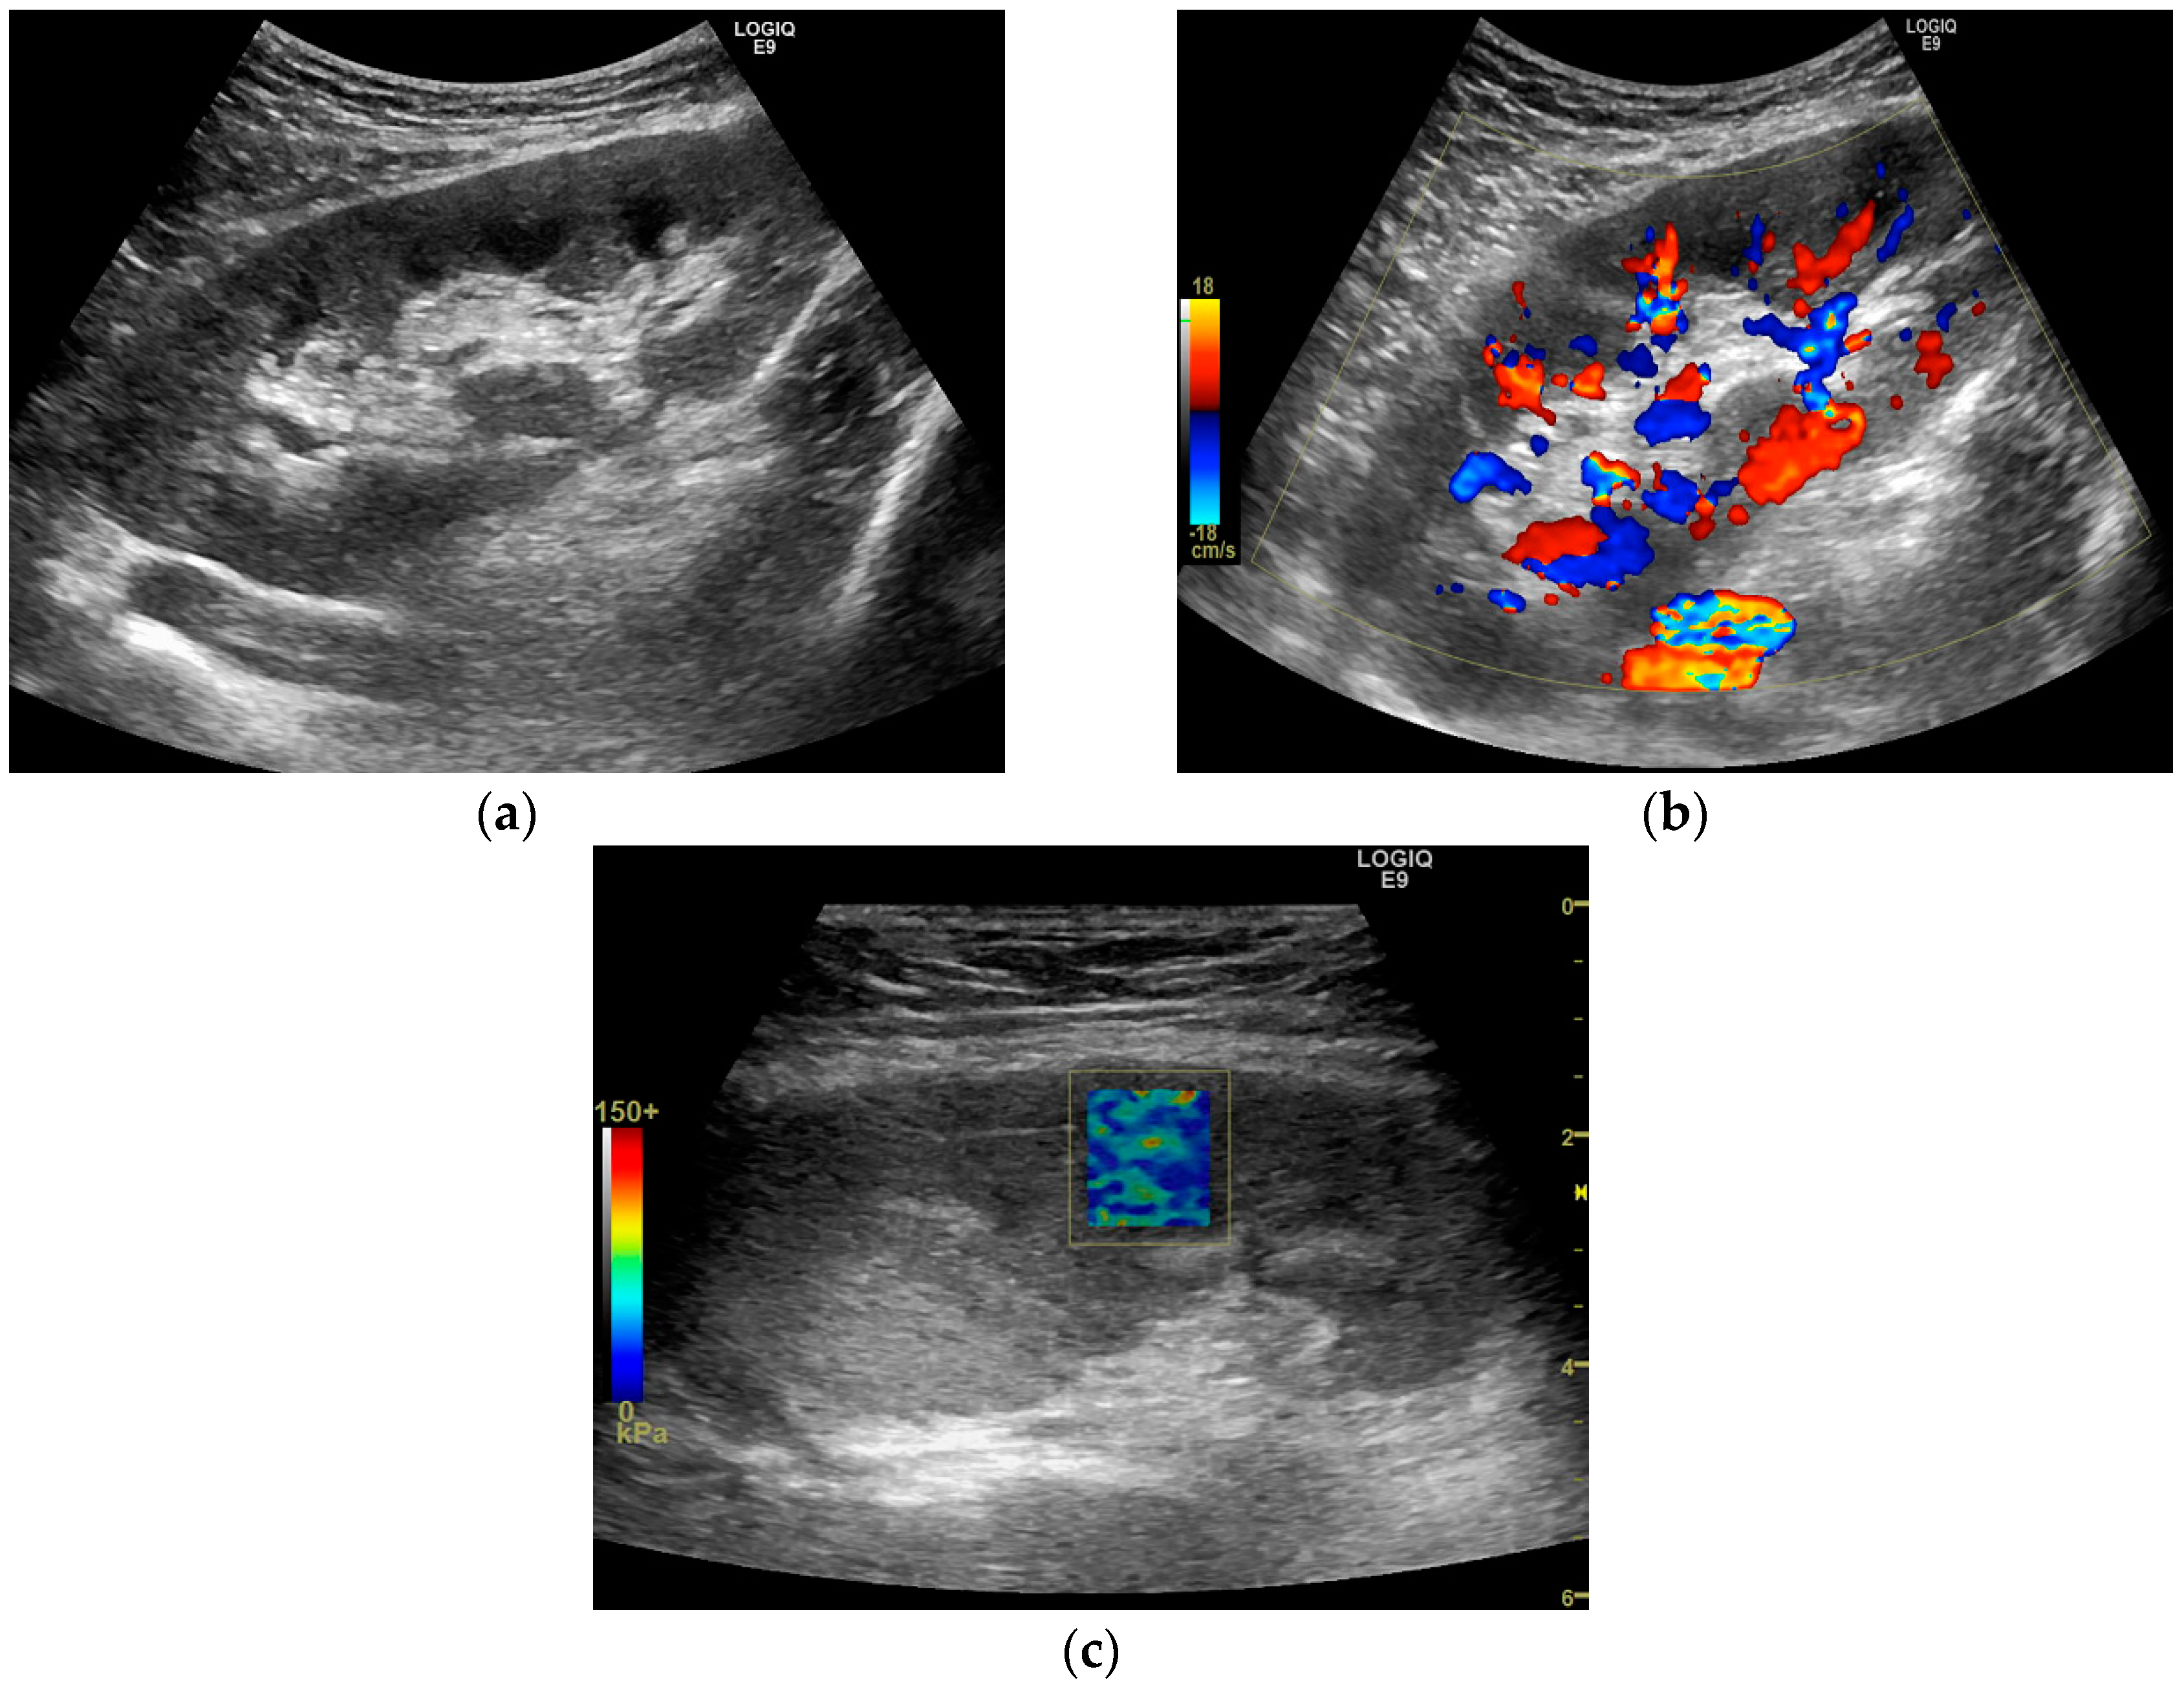

2.4. Shear Wave Elastography Examination